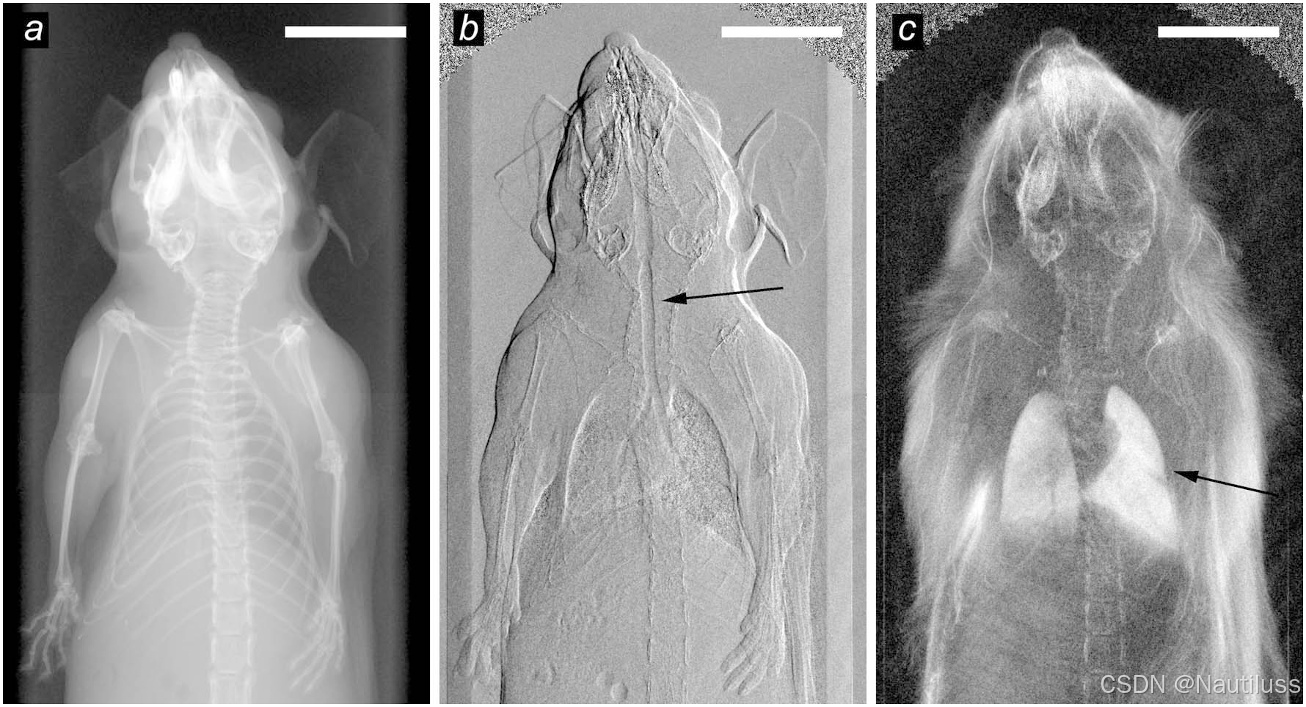

如图所示为小鼠体内多对比X射线图像。 (a) 基于衰减的传统X射线图像。 (b) 基于X射线折射的差分相位对比图像。 (c) 基于X射线散射的暗场图像。在图像 (b) 和 (c) 中用箭头标出了对比度增强的区域,展示了差分相位对比和暗场技术的能力。特别指出了气管的折射和肺部的散射。

基于吸收的传统X射线图像:该图像是使用传统X射线吸收原理创建的。它依赖于小鼠不同组织对X射线的差异吸收。

基于X射线折射的差分相位对比图像:通过差分相位对比技术获得该图像,捕捉X射线通过不同结构时的相位变化。

基于X射线散射的暗场图像:通过检测散射的X射线生成的暗场图像。它提供有关小鼠组织中X射线散射的信息。特别强调了肺部的散射,显示了对比度增强的区域。